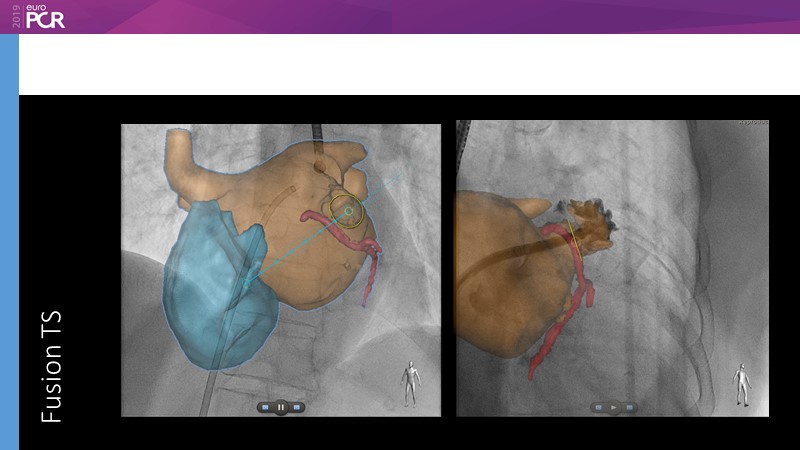

Pre-procedure planning

Previous Next

Optimising procedural outcome and safety